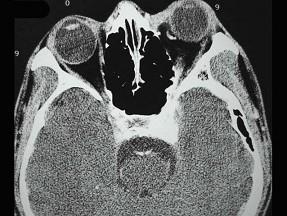

问题 男,44岁,车祸伤及右侧眉弓和头部,当时右眼上、下睑青紫淤血,半月后右眼球结膜高度水肿视力下降,右眼球突出,CT检查如图,最可能的诊断为()

选项 A.眶内静脉曲张 B.颈内动脉海绵窦段动脉瘤 C.海绵窦动静脉瘘 D.脑动静脉畸形 E.硬脑膜动静脉瘘

答案 C